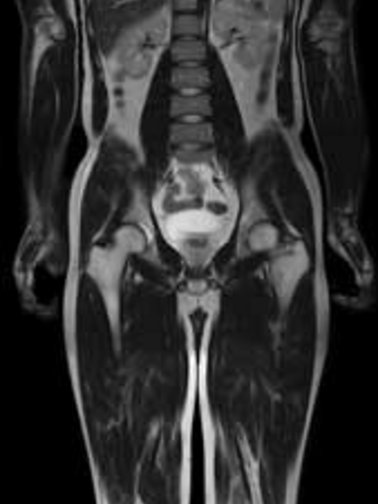

Bei der Kernspintomografie werden Schnittbilder des Körpers mittels eines starken Magneten (1,5 Tesla) und bestimmter Hochfrequenz-Spulen angefertigt. Diese Untersuchung hat keinerlei Strahlenbelastung. Es handelt sich um eine Magnetröhre die beidseits offen ist. Die Bilder ergeben einen hervorragenden Weichteilkontrast, so dass diese Untersuchungsmethode insbesondere für das Zentralnervensystem, die Wirbelsäule sowie Gelenke und den Bauchraum geeignet ist. Auch die Darstellung der Gallenwege und der Gefäße ist in der MRT möglich. Bei einem Teil der Untersuchungen ist ein Kontrastmittel notwendig. Dies wird intravenös gegeben.

Für Privatversicherte und Selbstzahler bieten wir eine Ganzkörper-MRT Untersuchung an, um in c.a. 45 Minuten alle Organe von Kopf bis Fuss "screenen“ zu können, ob etwas Krankhaftes vorliegt. Diese Untersuchung kann Krankheiten oder Tumore erkennen, bevor diese bemerkt werden.